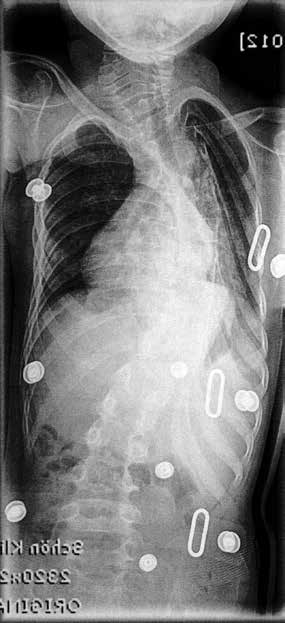

Lage und Funktionsrichtung der Druckzonen sind das wichtigste Kriterium für ein optimal korrigierendes Korsett. Diese müssen auch noch nach der Aufrichtung in der Orthese auf der richtigen Höhe liegen. Eine visuelle Überprüfung mit einem Dermographietest ist nur bedingt aussagefähig. Hierbei wird die Haut gegenüber den Druckzonen durch die Öffnungen in den Expansionsräumen durch leichtes Kratzen markiert, um diese Markierungen dann nach Abnahme des Korsetts mit den sich auf der Haut abzeichnenden Druckzonen in der Höhe zu vergleichen (5 S. 45). Aussagekräftiger ist allerdings immer ein Röntgenbild mit einer vorherigen Markierung der Druckzonen im Korsett mit Blumendraht, Büroklammern oder ähnlichen Markern (Abb. 8).